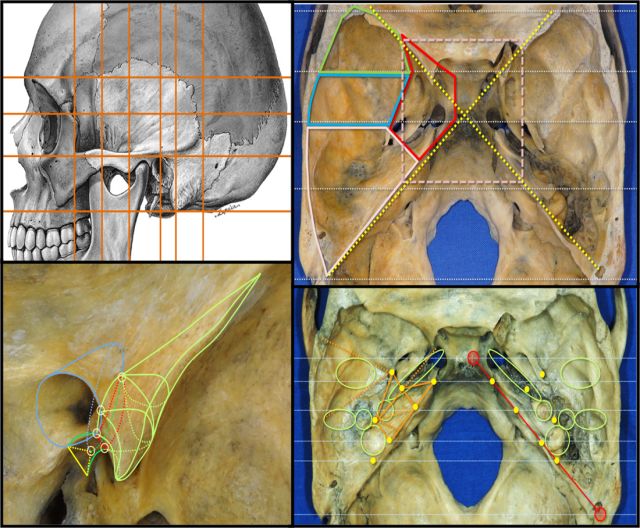

Samii临床神经解剖实验室

颅颈交界区显微解剖

小脑幕切迹显微解剖

前床突区域显微解剖

眶尖显微解剖